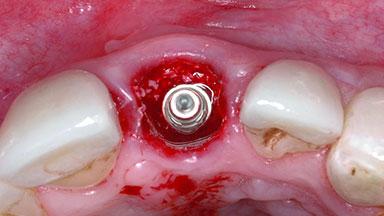

Replacement of a Failing Upper Left Central Incisor: Immediate Placement of an RC Bone Level Implant and Provisionalization

Placement Protocol Immediate implant placement

Socket Morphology Single-root socket

Socket Integrity Damage to one or more bone walls

Bone Volume Damage to one or more socket walls